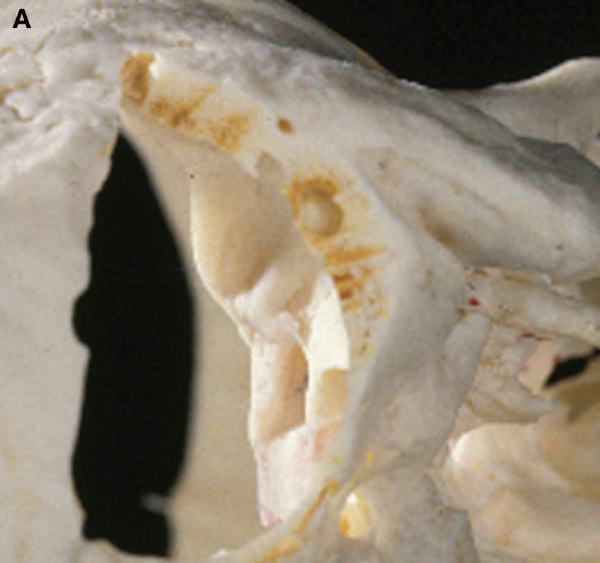

图1:枕下乙状窦后入路从术者视角展示的右侧CPA的解剖结构。患者仰卧位,头向对侧偏转。

耳蜗神经沿着前庭神经鞘瘤的下表面走形。下图:右侧前庭神经鞘瘤,大小约1.5cm。